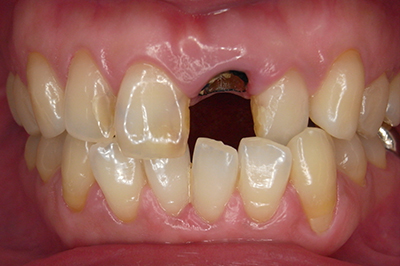

治療例2

歯ぐきが安定した状態

土台をたてた

噛める機能を回復

| ご費用 | 手術費用人工歯根 1本275,000円(税込) 上部構造 88,000円~110,000円(税込) |

|---|---|

| リスク・副作用 | 保険非適応(自費診療) 特定の全身疾患や持病のある方、顎骨密度の足りない方、妊娠中の方は手術ができない場合があります。 下顎のインプラント手術の際、偶発症のリスクがあります。 人工歯根が顎骨と癒着しないリスクがあります。 インプラント周囲炎になるリスクがあります。 |